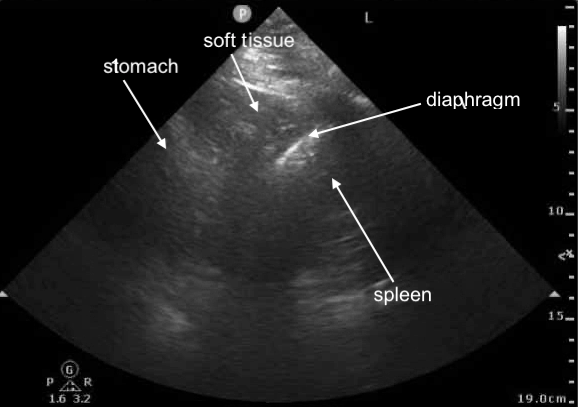

POCUS Image 1 - left mid-posterior axillary line, probe marker cephalad, attempt to visualize left hemidiaphragm

(not the best windows, structures a bit challenging to see clearly, we shall try our best with these)

POCUS Image 2 - left mid-posterior axillary line, probe marker cephalad, attempt to visualize left hemidiaphragm